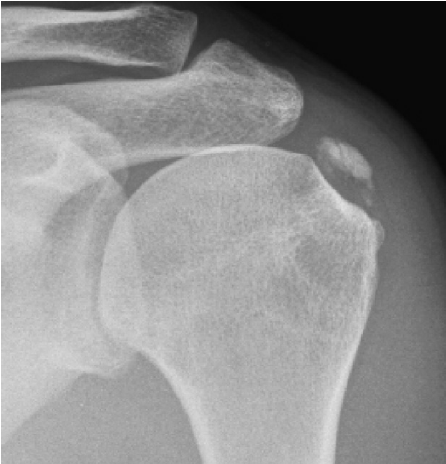

Poleg kliničnega pregleda je potrebna RTG diagnostika in UZ preiskava ramena, v določenih primerih tudi preiskava z magnetno resonanco. Običajno se vnetje zdravi s počitkom, analgetično terapijo, fizikalno terapijo. V določenih primerih svetujemo tudi terapijo z udarnimi valovi (ESWT).

V kolikor so kalcinati večji od 8mm in so enakomerne strukture lahko pod ultrazvočno kontrolo opravimo tudi punkcijo kalcinata in kalcinat izperemo. Poseg se opravi v lokalni anesteziji in traja približno 30 minut. Bolečina lahko traja tudi nekaj dni po posegu. V teh primerih svetujemo jemanje analgetikov. Nekaj dni po posegu priporočamo postopno stopnjevanje aktivnosti, izvajanje vaj, plavanja, nordijske hoje in fizikalne terapije in po 2 -3 mesecih vrnitev željenim aktivnostim.